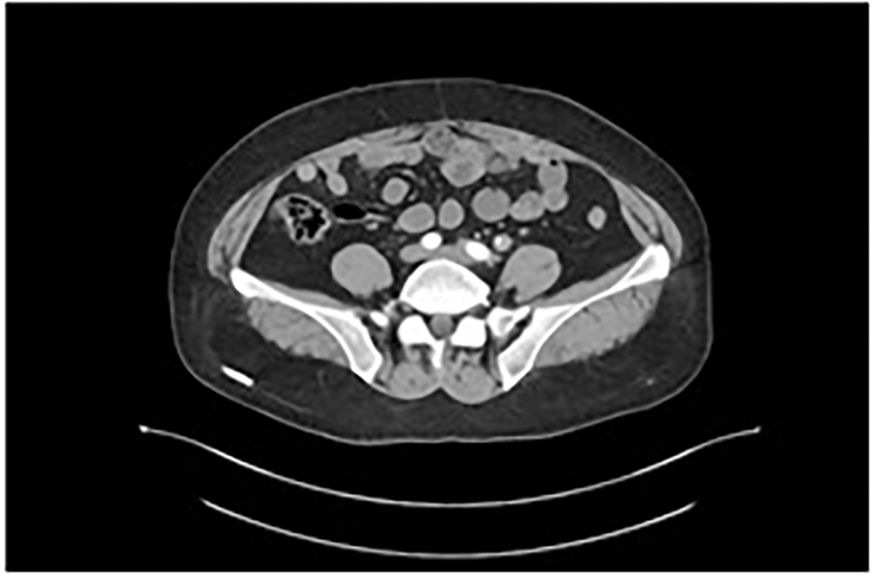

Figure 2

Microscopic view of tissue showing densely packed cells with varying shades of pink and purple. The image displays a complex network of cells, possibly indicating a histological sample.

Figure 2. Histological section of the resected ureter (Hematoxylin and eosin staining, ×200), showing residual small cell neuroendocrine carcinoma with muscularis propria infiltration.